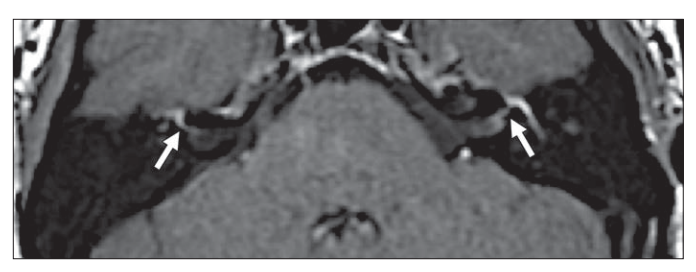

图8,T1增强,Bell麻痹患者,左侧面神经颅内段、迷路段、膝状神经节、鼓室段、迷路段较对侧均明显增强

图10,T2相,面肌痉挛

患者可见血管压迫面神经,以小脑前下动脉多见